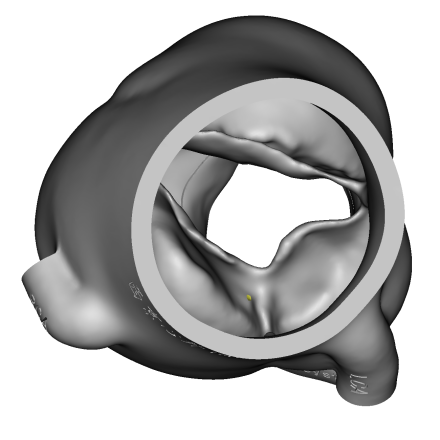

3D打印体外模拟:

体外模拟植入29mmJ-Valve瓣膜,升主动脉侧(左图)观察可见定位键挂于无冠瓣上导致瓣架无法到达瓣环位置,左室流出道侧(右图)观察可见瓣架底端距离瓣环平面18mm,且J-Valve在瓦氏窦中呈倾斜状态。